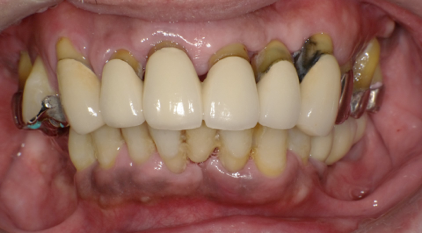

術直後の写真です

オールオン6本のインプラントをいれました

初期固定もよかったので即時荷重をおこなっています

術後2週間 傷もきれいに治ってきています